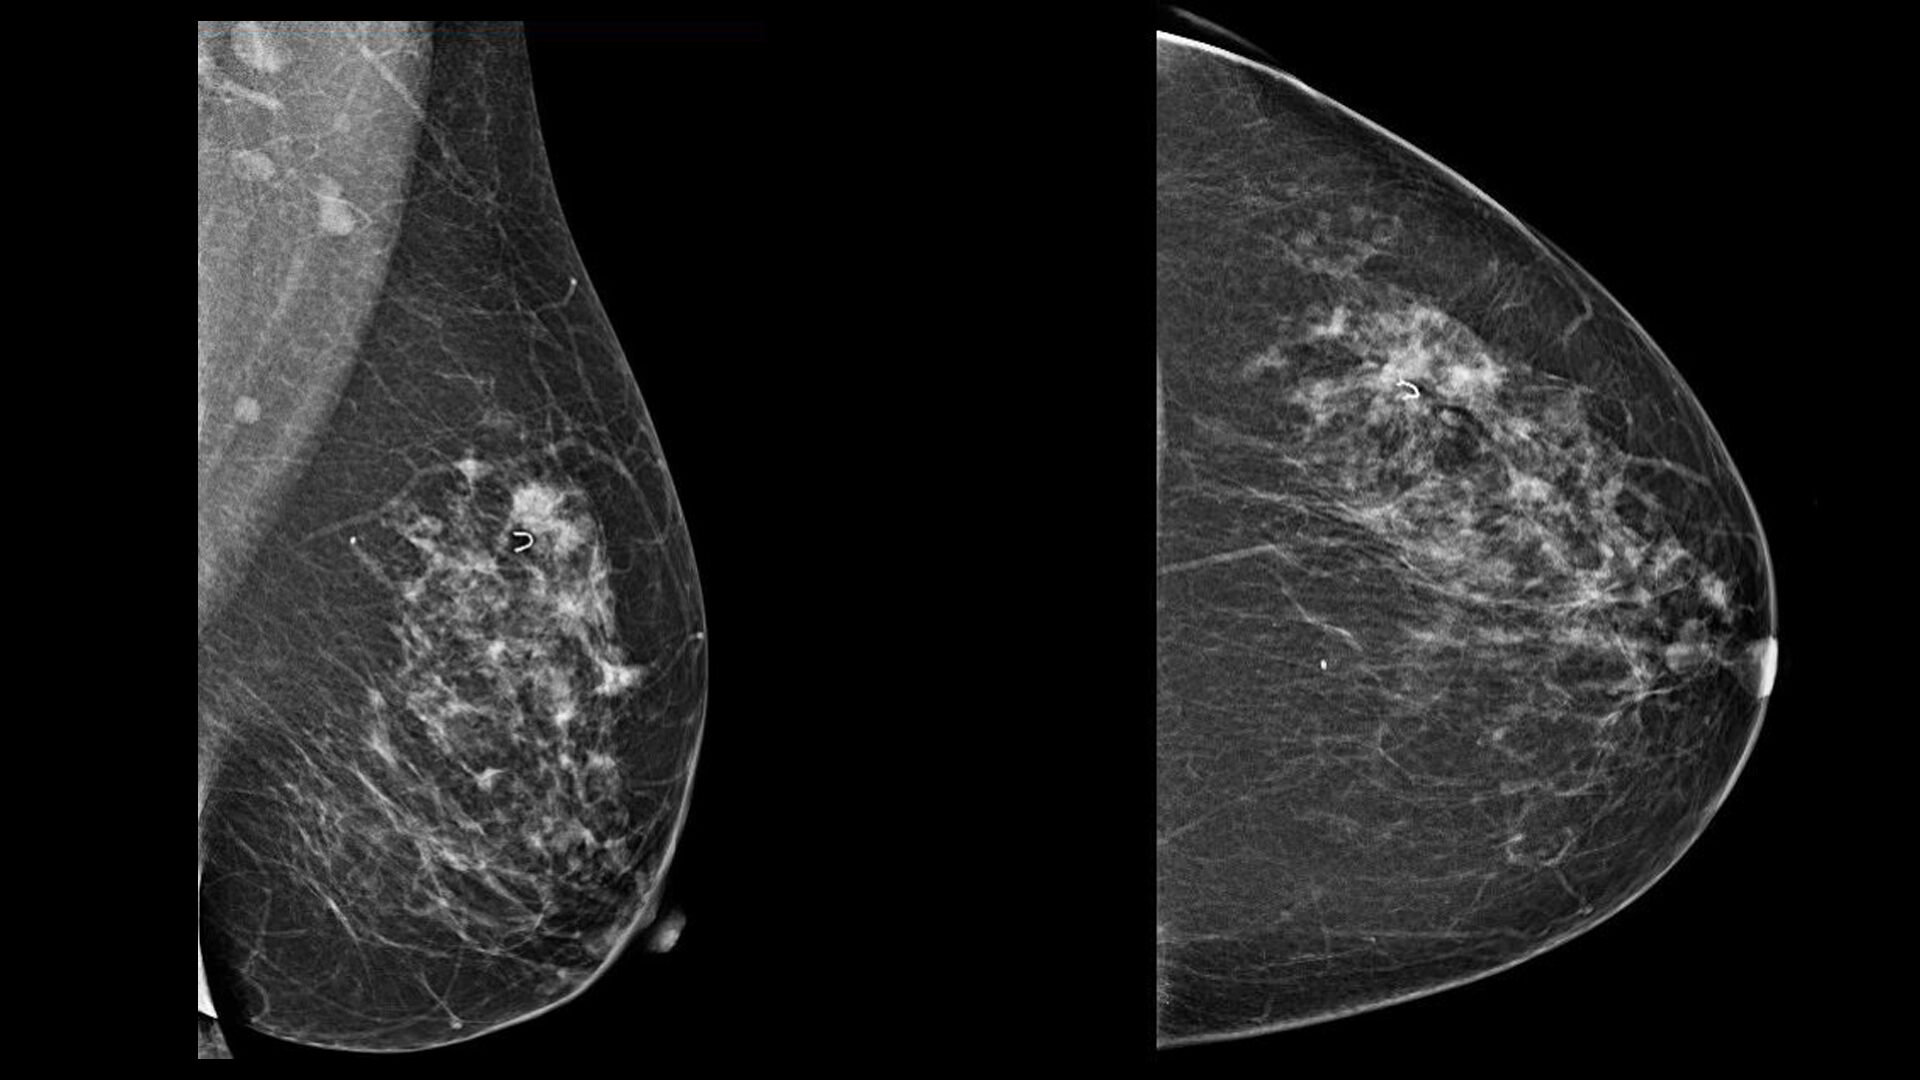

Злокачественные опухоли молочных желез

Фиброаденома молочной железы - доброкачественное образование, которое часто встречается у женщин. Оно может быть обнаружено при помощи различных методов диагностики, включая маммографию. Ниже представлены фотографии, помогающие понять, как выглядит данное заболевание.

Маммография и ее роль в диагностике фиброаденомы молочной железы

Маммография - это рентгенологическое исследование молочных желез. Оно позволяет выявить различные изменения в тканях, включая фиброаденому. На маммограммах можно увидеть структурные особенности опухоли и отследить ее динамику во времени.